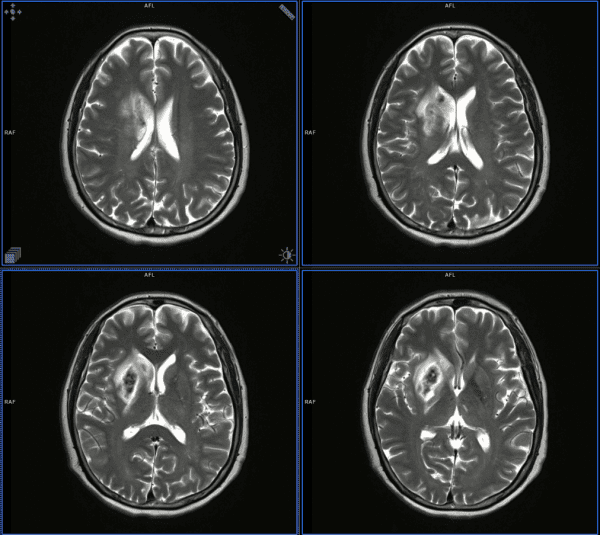

Xuất huyết não

» Thông tin: Nam giới – 61 tuổi.

» Lâm sàng: Tai biến mạch máu não.